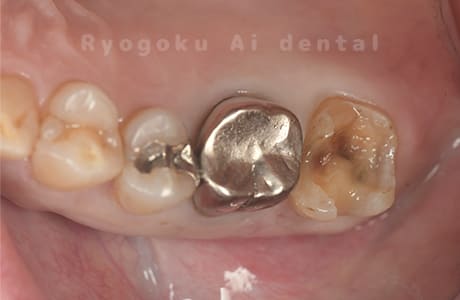

Case11

- 治療内容

- セラミッククラウン、セラミックインレー

- 治療費用

- 123,000円×2(セラミッククラン)、77,000円(セラミックインレー)

銀歯が取れて、ご来院された患者様です。奥歯2本をセラミッククラウン、手前の小臼歯をセラミックインレーで治療を行いました。